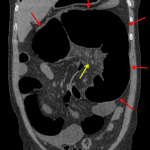

- Gaseous distension of multiple loops of small and large bowel with a dilated loop of colon in the left upper quadrant measuring up to 11 cm in diameter

- Multiple small bowel and colonic air-fluid levels on upright imaging

- Paucity of distal colonic gas

- Cecal volvulus

Gaseous distension of multiple loops of small and large bowel, including a markedly dilated loop of colon in the left upper quadrant, with multiple air-fluid levels on upright imaging and paucity of distal colonic gas, which raises concern for bowel obstruction. Recommend CT for further evaluation.